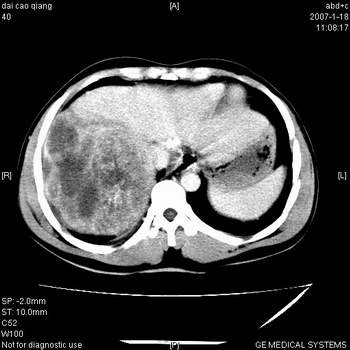

符合巨块型肝癌表现:

1、平扫低密度,增强后表现为快进快出。

2、动脉期可见迂曲的动脉供血血管

3、并可见门静脉右支癌栓形成

4、可见假包膜

5、腹主动脉旁结节影,考虑肿大淋巴结。

典型的肝右叶巨块型肝癌破裂、门脉瘤栓形成。

肝右叶巨大不均匀低密度肿块,前缘有假包膜,增强明显的呈快进快出表现,门脉右支有癌栓,病人虽然年轻但还是首先考虑肝右叶巨块形肝癌,病人血象高只能说有合并感染。不支持肝脓肿。